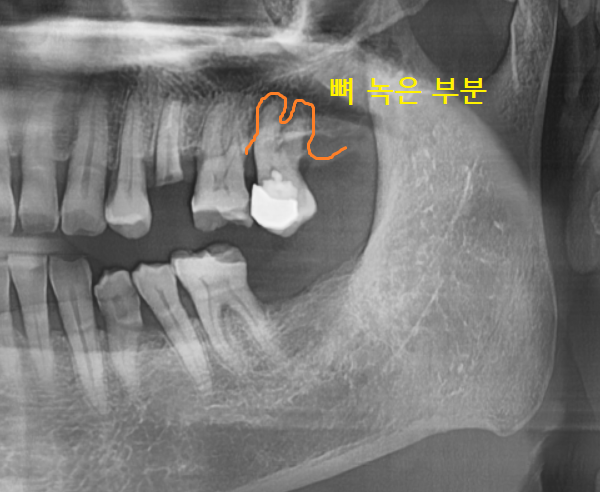

임플란트 진단을 위해 ct를 찍어보았는데

다른 치아도 뼈가 많이 녹은 것이 발견

환자분께 안 좋은 상황임을 안내해드렸습니다.

231211

부러진 치아 바로 옆에였는데요.

하셨던 아말감 충전된 상태도 안좋았지만

잇몸 뼈가 많이 녹으셨어요.